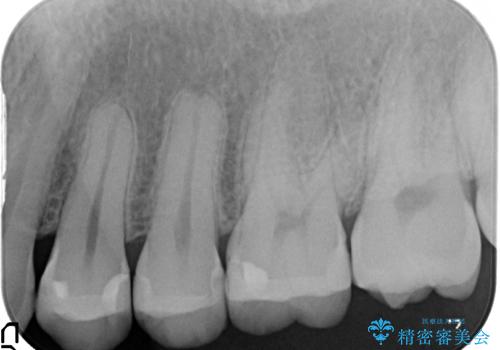

- 虫歯の治療を希望されて来院された患者様です。

歯と歯の間の虫歯が多く、同じブロックの歯をまとめて治療していくこととしました。

今回、幸いにもそんなに大きな虫歯がなかったため、虫歯をとって、セラミックインレーにて修復することが来ました。